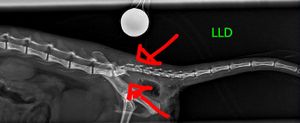

Ela sofreu múltiplas fraturas na pelve e na coluna, além de lacerações nas patas. O quadro é muito sério e ela corre risco de ficar paraplégica.